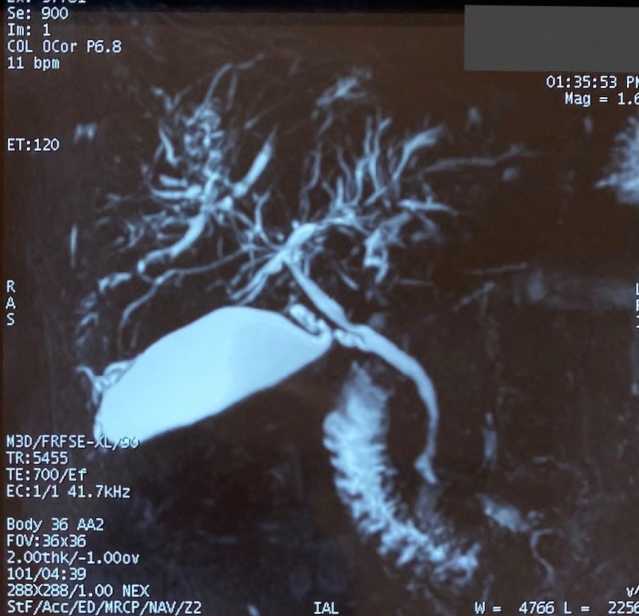

С учетом выявленных изменений по данным эластометрии и наличии повышенного уровня ГГТП пациентка направлена на магнитно-резонансную холангиопанкреатографию (МРХПГ) для дополнительного поиска причин синдрома холестаза.

МРХПГ: МР-признаки фиброза внутрипеченочных желчных протоков, определяются диффузные мультифокальные кольцевидные стриктуры, чередующиеся с участками нормальных внутрипеченочных желчных протоков, множественные короткие тяжеобразные стриктуры (рис. 3).

Рис. 3. Результаты МРХПГ пациентки В